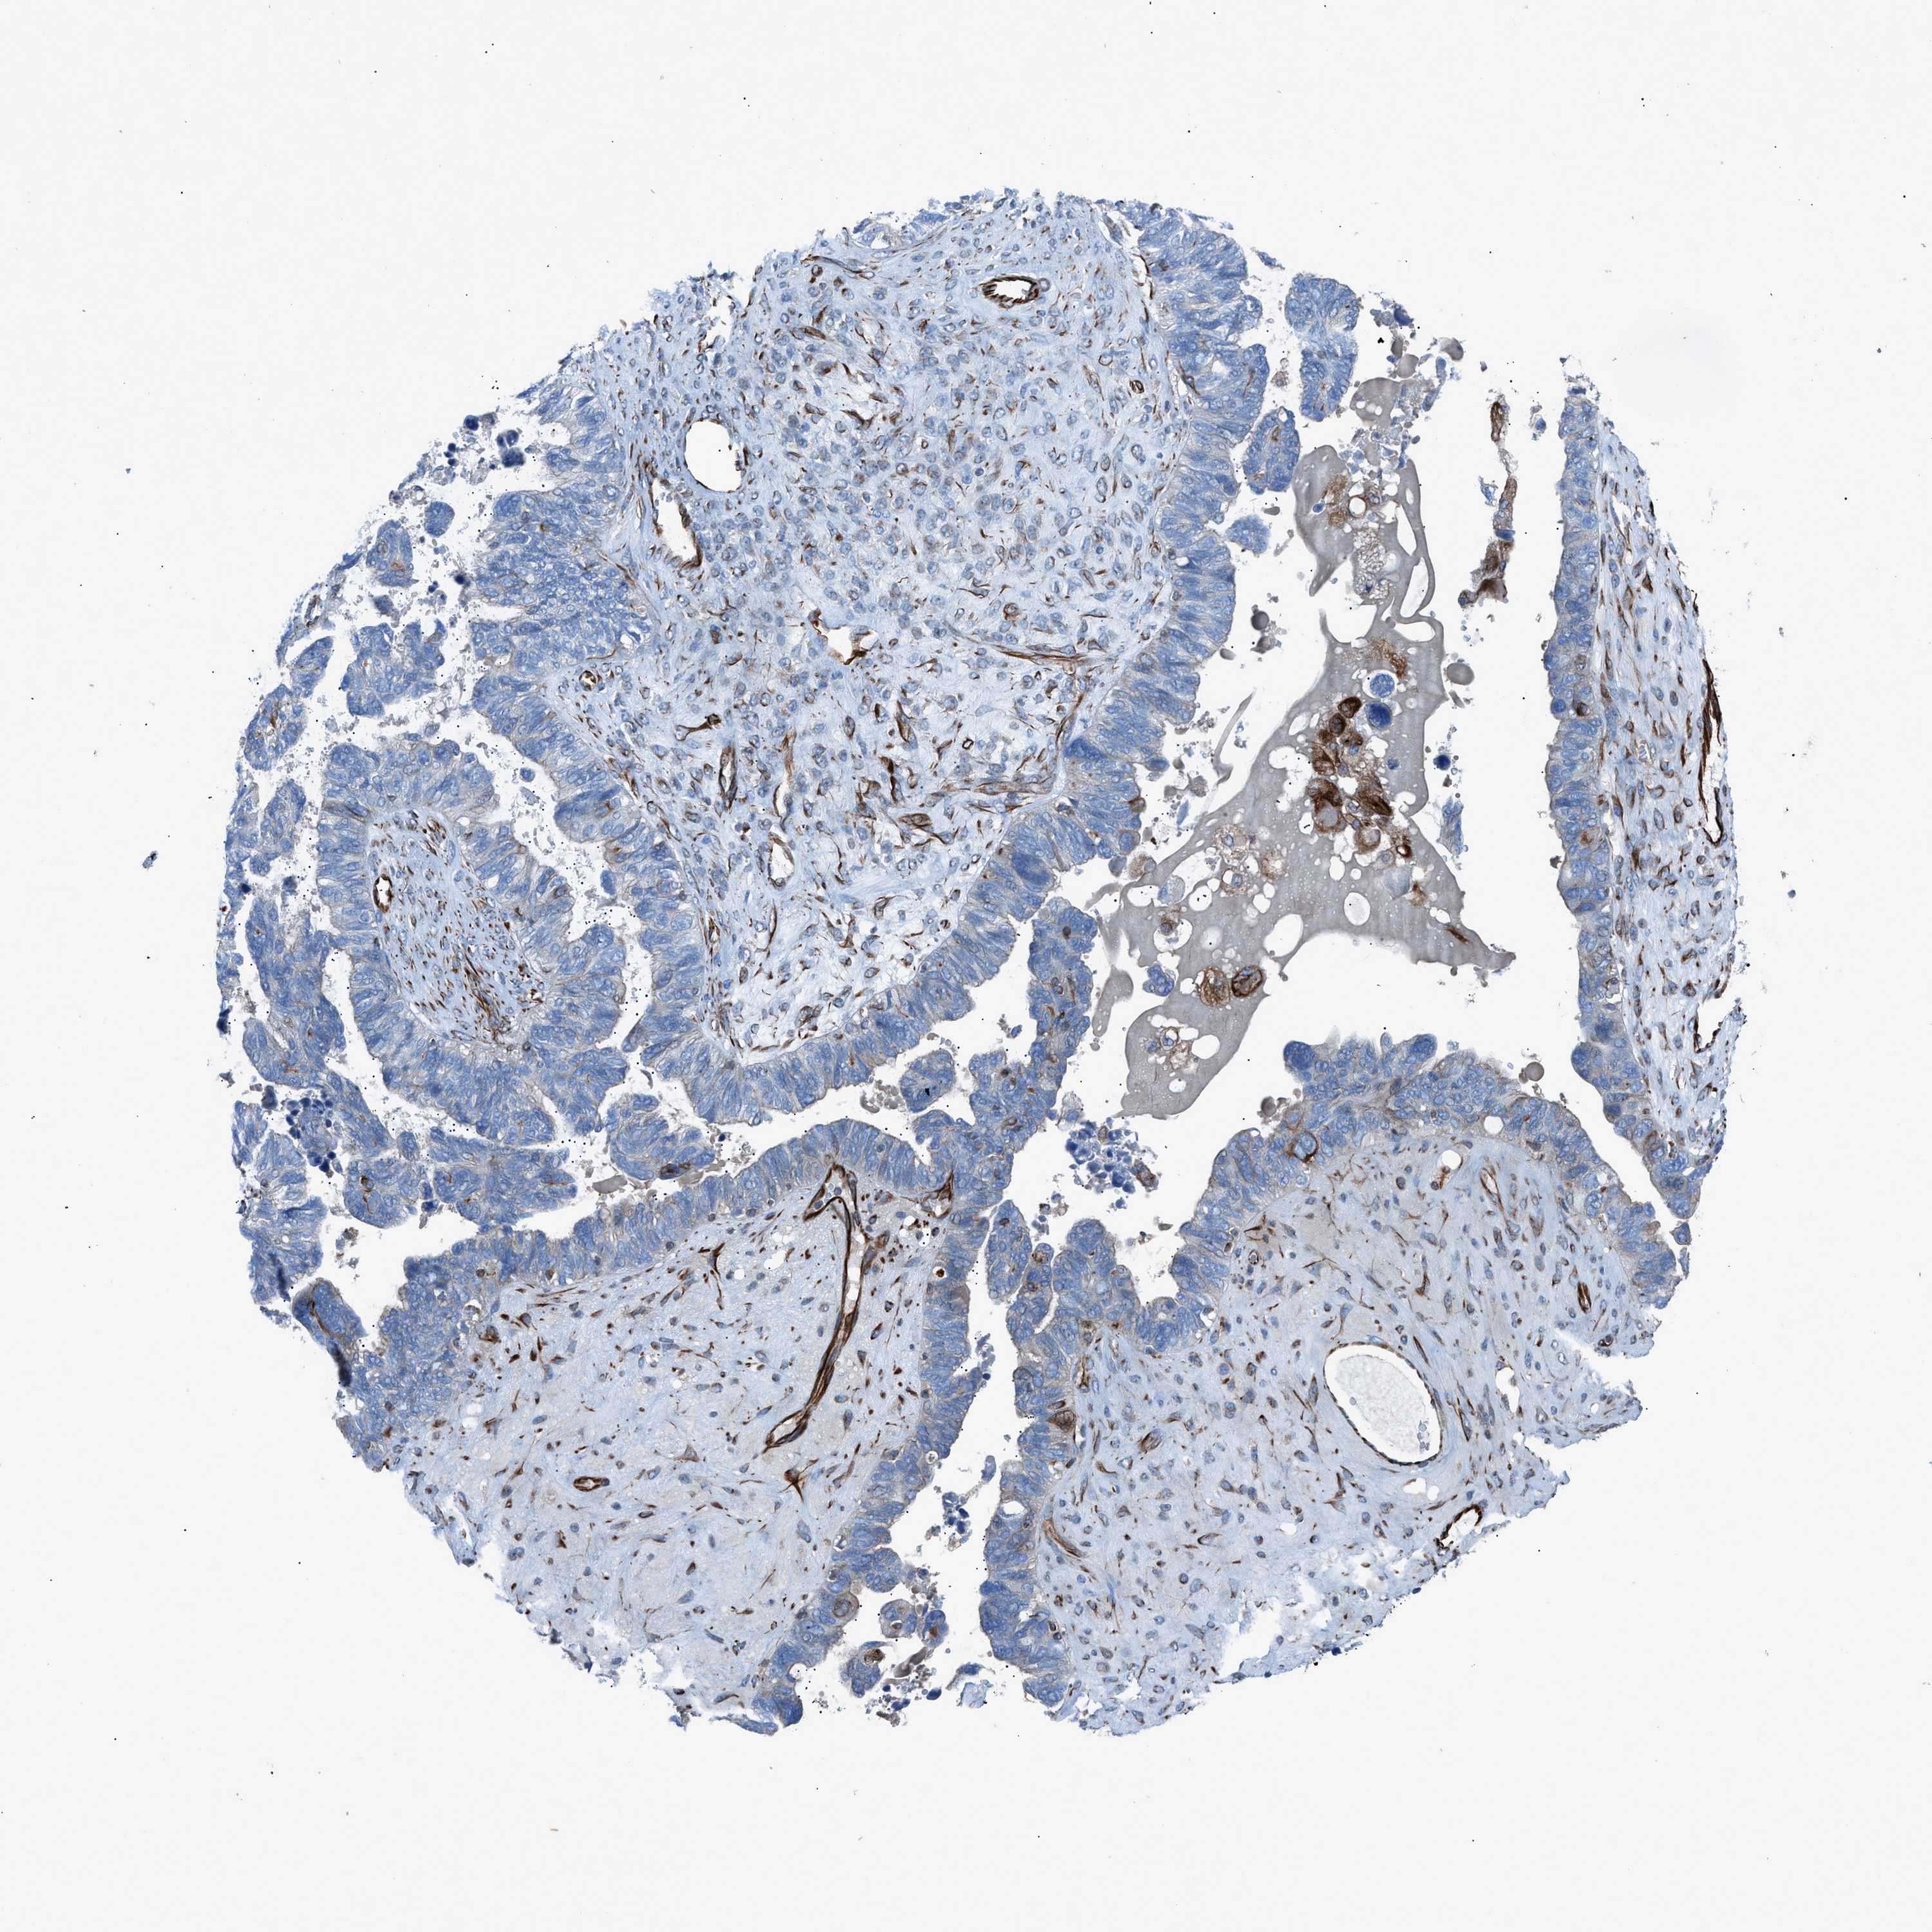

OVARIAN CANCER - Protein expressioni

A mouse-over function shows sample information and annotation data. Click on an image to view it in a full screen mode. Samples can be filtered based on level of antibody staining by selecting one or several of the following categories: high, medium, low and not detected. The assay and annotation is described here.

Note that samples used for immunohistochemistry by the Human Protein Atlas do not correspond to samples in the TCGA dataset.

Antibody stainingi

Antibody staining in the annotated cell types in the current human tissue is reported as not detected, low, medium, or high, based on conventional immunohistochemistry profiling in selected tissues. This score is based on the combination of the staining intensity and fraction of stained cells.

Each image is clickable and will lead to virtual microscopy that enables deeper exploration of all samples and also displays staining intensity scores, fraction scores and subcellular localization as well as patient and tissue information for each sample.

Antibody HPA016439

Cystadenocarcinoma, serous, NOS

Carcinoma, endometroid

Cystadenocarcinoma, mucinous, NOS

Carcinoma, NOS